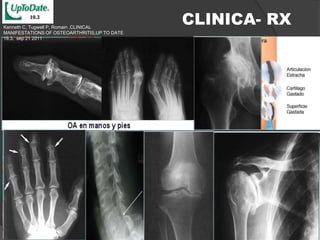

Kenneth C, Tugwell P, Romain ,CLINICAL

CLINICA- RX

MANIFESTATIONS OF OSTEOARTHRITIS,UP TO DATE

19,3, sep 21 2011